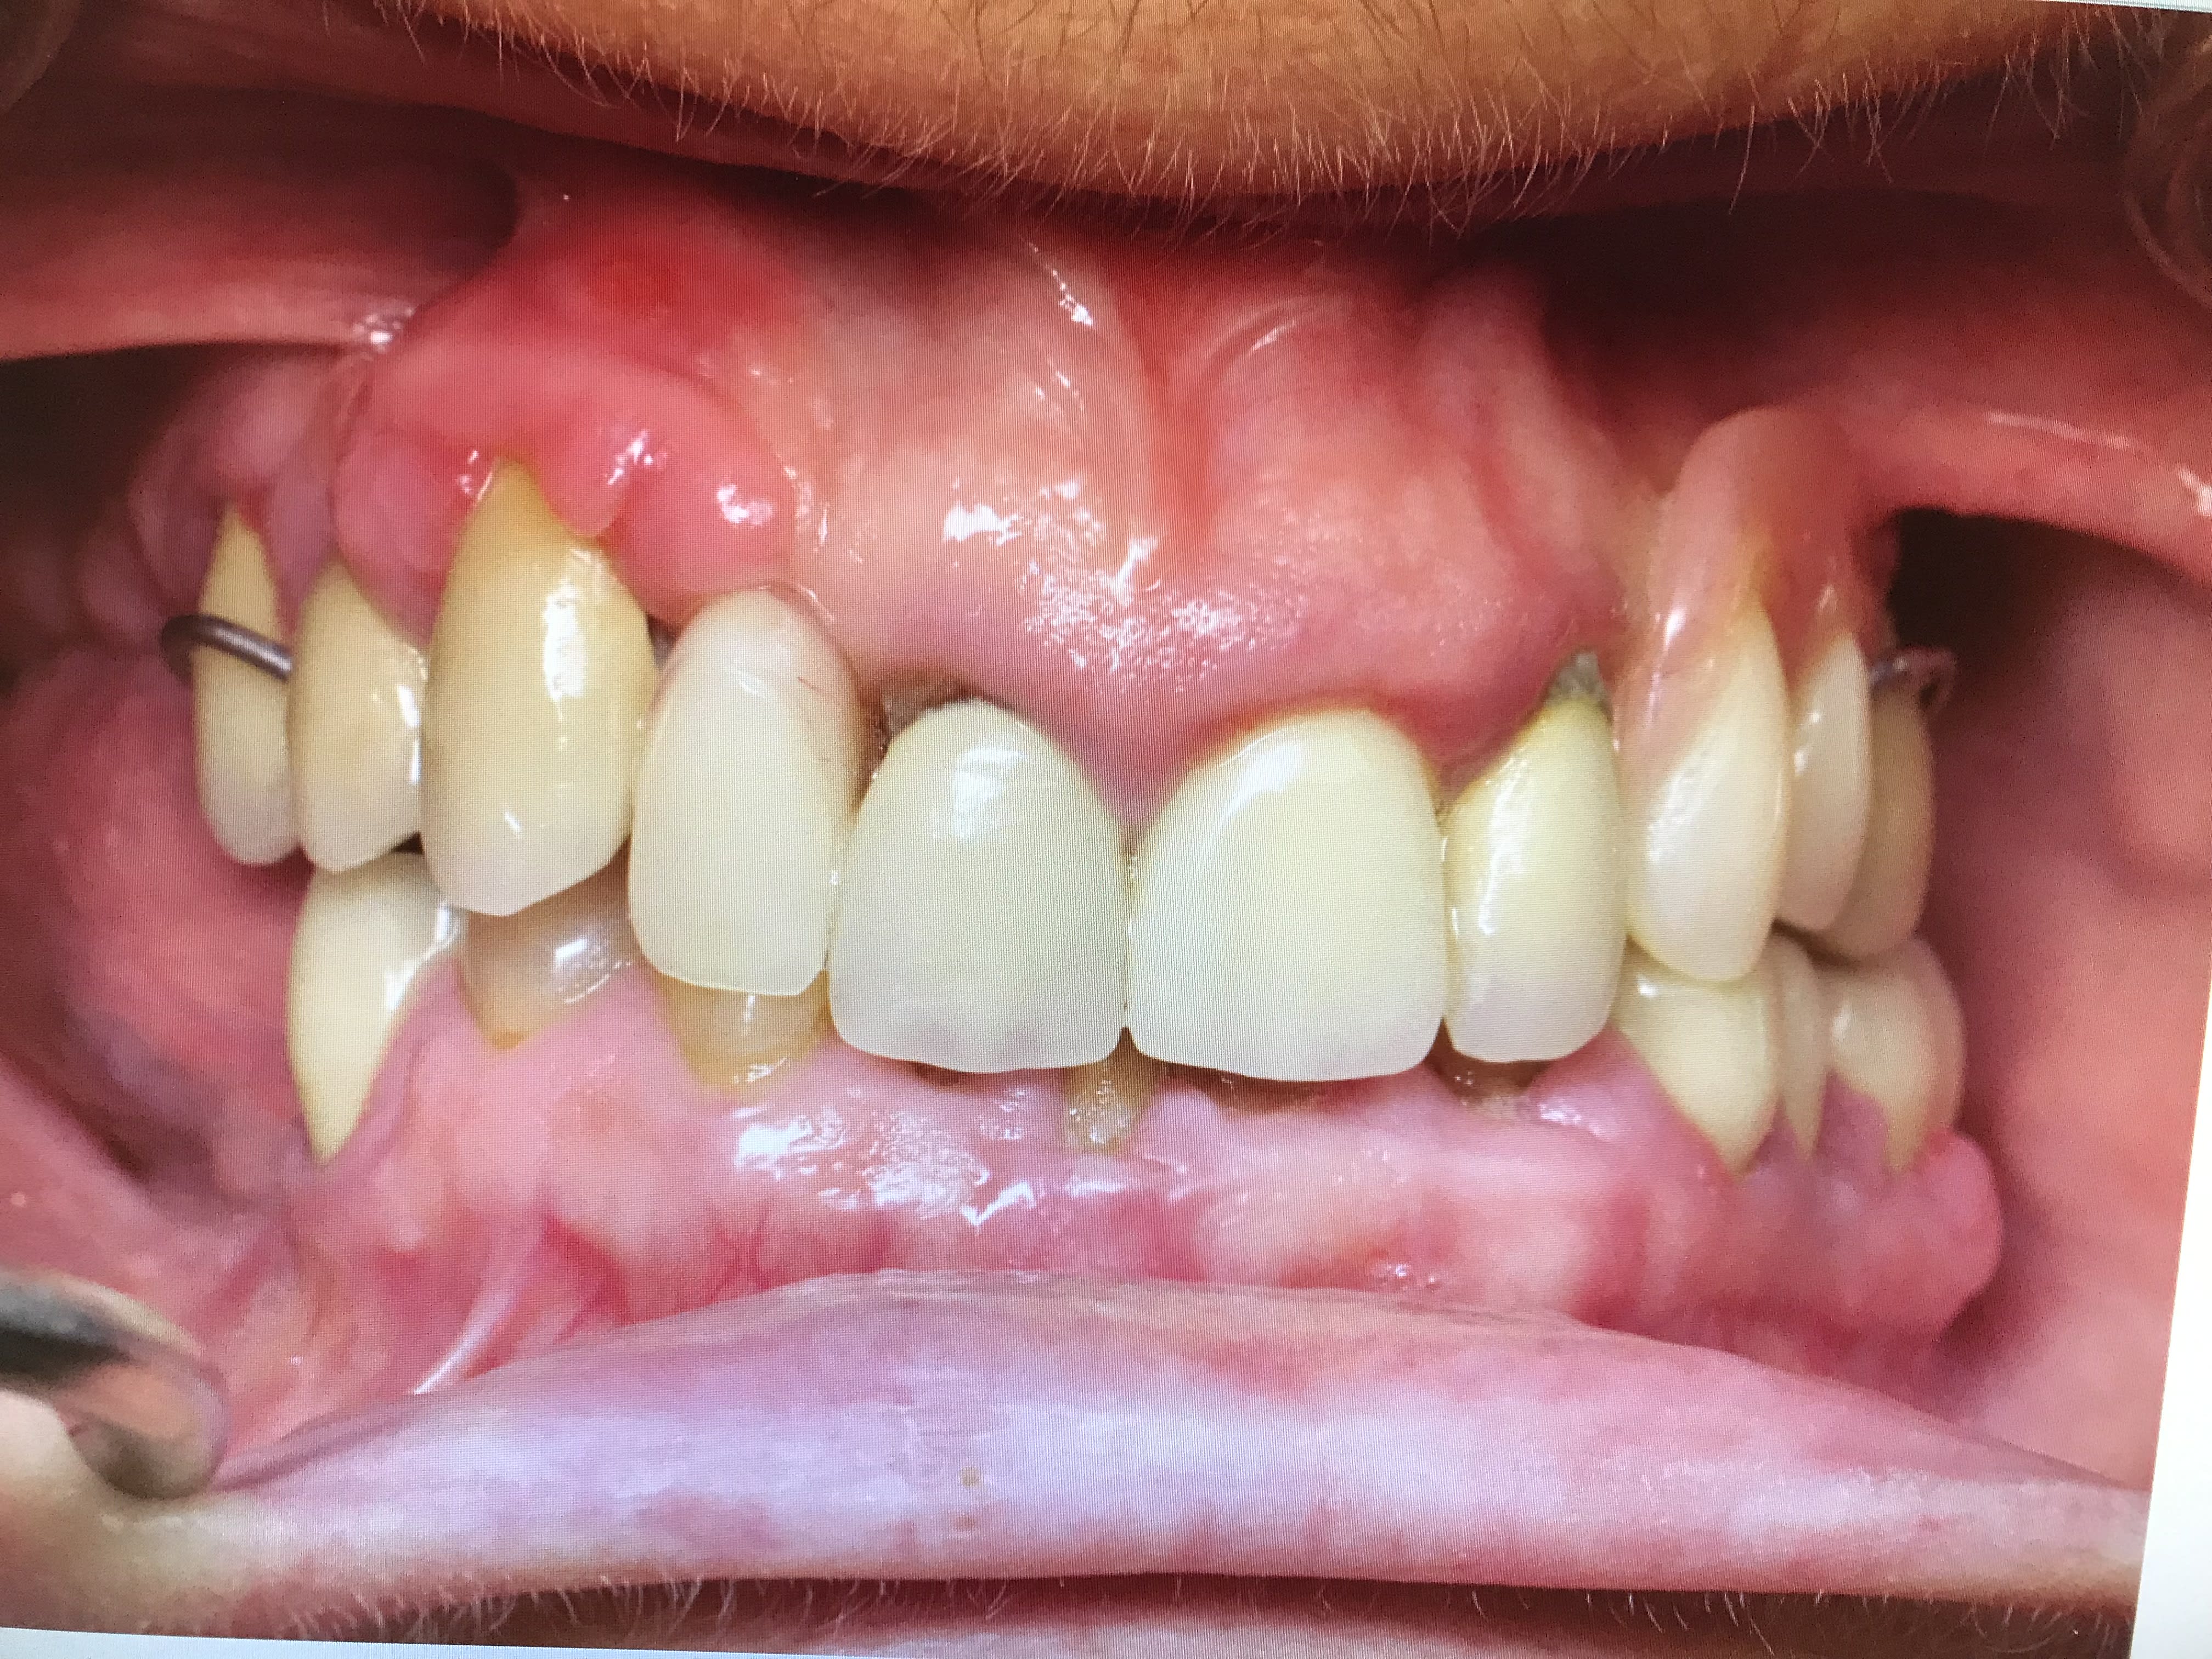

Patiente avec pilier de bridge 13 fracturé + 15 paro mobile + 25 paro mobile + 22 légèrement mobile. Les seules dents "viables" sur l'arcade sont 11, 21 et 22 et la 12 a été extraite entre temps.

Patiente avec grosse supraclusion et sourire gingival.

Elle ne veut pas de solution amovible.